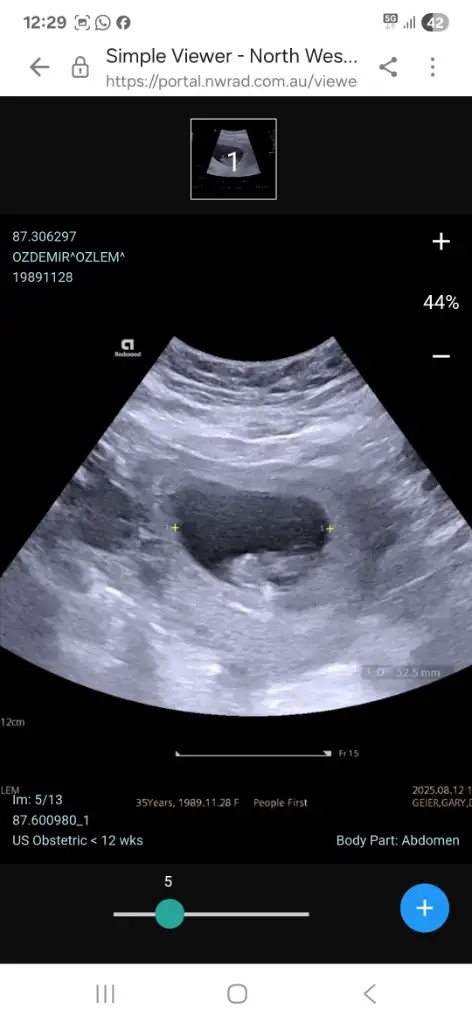

Arkadaşlar merhaba daha önce burada ultrason fotoğrafına bakıp cinsiyet tahmin edenleri görmüştüm benim içinde bi heyecan olur:) var mıdır tahmininiz normalde 12+4 üm ama ultrasonda 13 haftalık görünüyor.

Benimde 13+1 de karından ultrason ile bakıldı tahmin de bulunabilir misiniz 🙏